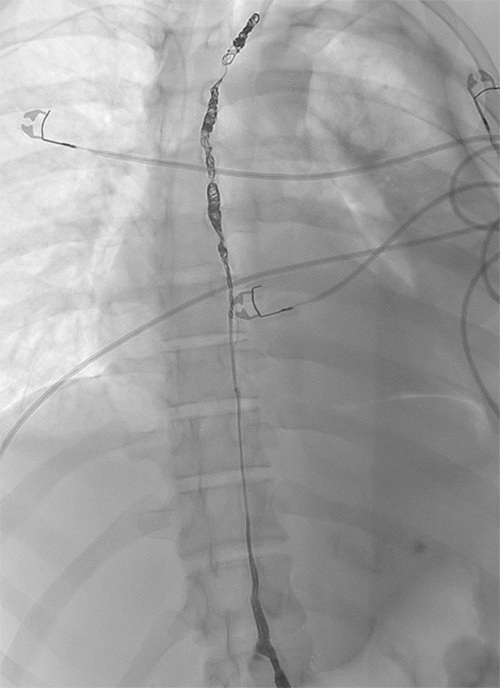

Interventional radiology performed a lymphangiogram to evaluate lymphatic drainage of the pelvic, abdominal, and thoracic regions. The study identified active extravasation from the thoracic duct near the clavicular head. The interventional radiologist then embolized the leaking segment using coils and glue (Figures 3-6). While chest tube drainage briefly declined, it returned to pre-procedure levels by postoperative day 2.

Figure 3. Early Filling of Cisterna Chyli over L1 (arrow). Published with Permission

Figure 4. Lymphangiogram via Inguinal Lymph Node Cannulation Demonstrating Opacification of Lumbar Nodes, Cisterna Chyli, and Lower Thoracic Duct. Published with Permission